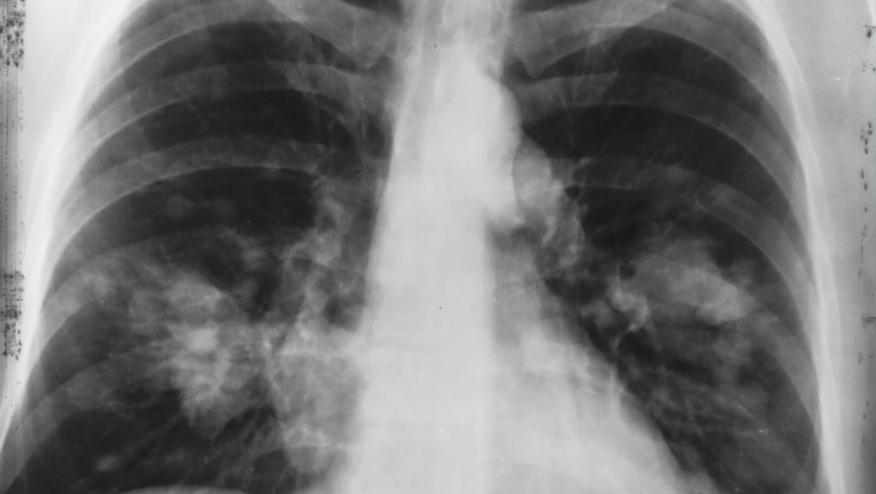

Interstitial Lung Disease and Lung Cancer Risk Save

A large prospective cohort study found that interstitial lung disease (ILD) is associated with an increased risk of lung cancer.